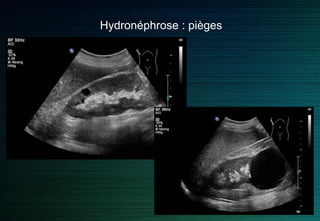

Hydronéphrose : pièges

Hydronéphrose grade II

Epanchement loge rénale important

Ne pas confondre avec un épanchement dans la loge de Morison